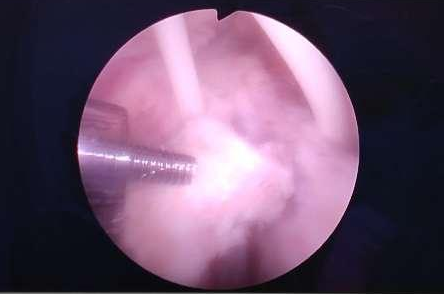

五、肩关节镜肩袖肌腱损伤手术技术。肩关节大师Avi Chezar教授对肩关节的深入理解、对关节镜的熟练操作,着实让我大开眼界。从Avi Chezar教授身上,我学到的不仅仅是更精湛的手术技术,更多的是先进的手术理念、对手术的思考方式、如何去对手术做全面的评估与设计。

七、全关节镜下Latarjet手术。复发性肩关节脱位、肩关节不稳的治疗是世界性难题,如何稳定患者的肩关节、避免肩关节脱位的复发非常具有挑战性,其治疗目前尚未有高度凝聚性的共识。在EMEK医学中心,Avi Chezar教授成熟开展的全关节镜下Latarjet手术,极大地降低了患者肩关节脱位的复发率,让肩关节不稳这一世界难题变得不再那么遥不可及。